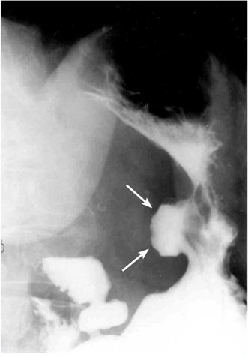

צילום קיבה בעזרת חומר ניגוד - האבחנה הרנטגנית חשובה במיוחד להבדיל בין כיב שפיר לממאיר. הכיב השפיר בצילום בולט מעבר לדופן, ואילו בכיב ממאיר הכיב נמצא בפגם מילוי, ולפיכך אינו בולט מעבר לדופן. ב-90% מהכיבים אפשר להבדיל בין שני הסוגים הללו. כיבים שפירים נמצאים ברובם בעקומה הקטנה באזור האינסיסורה, ואילו כיבים באזור העקומה הגדולה הם בדרך כלל ממאירים (תצלומים 8.3 ו-9.3).